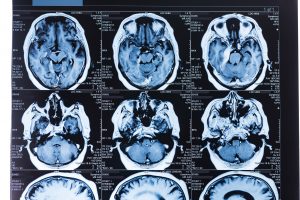

Mehr erfahren zu: "MRT: Differenzierung niedriggradiger von hochgradigen Meningeomen" MRT: Differenzierung niedriggradiger von hochgradigen Meningeomen Die Kombination bestimmter Magnetresonanz-Diffusions-Tensor-Bildgebungs-(MR-DTI) Parameter kann atypische/anaplastische, also hochgradige von niedriggradigen Meningeomen mit einer diagnostischen Genauigkeit von 96,2% differenzieren, so lautet das Fazit eines türkischen Expertenteams. Bei den Parametern handelte […]

Mehr erfahren zu: "Vorsorgliche Schädelbestrahlung auch beim nicht kleinzelligen Lungenkrebs?" Vorsorgliche Schädelbestrahlung auch beim nicht kleinzelligen Lungenkrebs? Lungenkarzinome neigen zur Metastasierung in das Gehirn – und das Auftreten von Hirnmetastasen verschlechtert meistens die Lebensqualität der Patienten massiv.